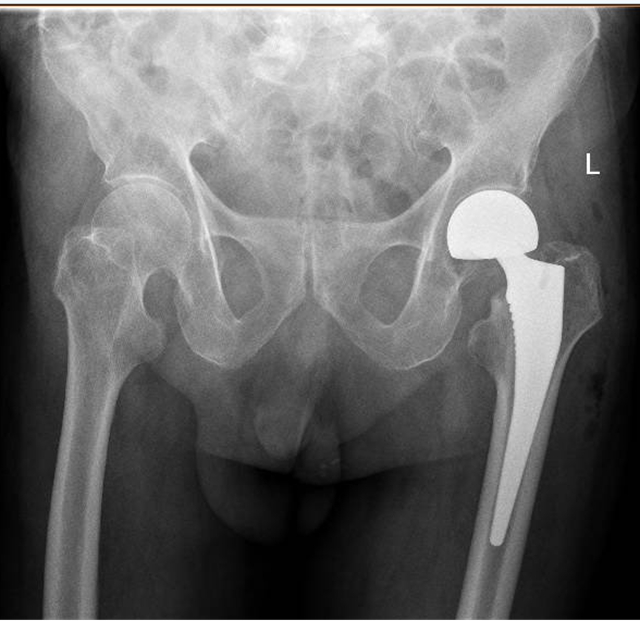

“王大爷入院时,检查发现左侧股骨颈骨折,也就是我们常说的‘髋关节骨折’。老人发生髋关节骨折,也被称为‘人生最后一次骨折’,死亡率近60%。让人痛心的是很多老人是死于骨折后长期卧床导致的并发症。”泸州市中医医院骨科主治医师吴东海介绍,老人发生骨折后,如果采用保守治疗,长期卧床容易发生压力性损伤、尿路感染、肺部感染等并发症,生活质量几乎无从谈起,更有可能因并发症威胁到生命。比较好的解决方案是尽快进行手术,让老人重新站起来,减少并发症的发生,提高生活质量,也减轻家人的负担。

“通过团队的默契配合,王大爷的手术我们仅用30多分钟就顺利完成,术中出血量不到50ML,做到了手术时间少,出血少,把各种风险降低到最小化。手术后,配合术后护理、内科治疗、中医手法康复等,让老人获得了快速康复。”吴东海说,随着技术的进步,越来越多的高龄患者得益于先进的综合治疗方法,这将让更多的高龄患者提高生活质量,重新焕发新活力。

骨伤三科重点专业技术:髋、膝骨关节外科、运动医学关节镜技术等关节伤病的治疗。以收治髋膝关节疾病和运动医学(关节镜)损伤治疗为主的特色科室。主要是对髋、膝关节疾病如先天性髋关节复位、髋关节发育不良、股骨颈骨折、股骨头坏死、股骨粗隆骨折、膝关节周围骨折、髋膝关节炎、膝关节半月板、交叉韧带损伤、肩踝运动损伤疾病等综合治疗,采用现代先进理念和技术进行股骨头坏死早期控制、髋、膝关节置换、骨折的内外固定等治疗手段,帮助患者最快恢复健康。关节镜专科治疗各种关节疾病,如关节半月板损伤、膝关节叉韧带断裂,肩周炎、肩袖损伤、踝关节滑膜炎、关节游离体取出、关节软骨损伤修复重建等。